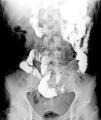

Tránsito intestinal, proyección anteroposterior de abdomen a los 50 minutos tras administración oral del medio de contraste. Se observa paso adecuado del medio de contraste por el duodeno y yeyuno. Se visualiza un estrechamiento abrupto del calibre de la luz del íleon en un trayecto de 10cm, identificándose paso filiforme del medio de contraste que mide, en su diámetro anteroposterior 1.5mm, «signo de la cuerda» (flechas), sugerente de enfermedad de Crohn.